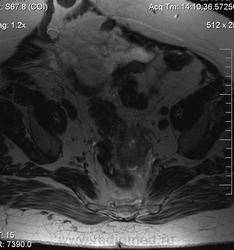

очень характерная картина для метастаза рака яичника, к сожалению.

Не могу достоверно определить локализацию метастаза брюшной полости, вероятно в лимф. узел с инвазией оободочной кишки. Рецидив С-r левого яичника думаю, что с инфильтацией левой стенки прямой кишки и культи влагалища, вторичная лимфаденопатия л/у малого таза. каликопиелоуретероэктазия (инвазия нижних отделов левого мочеточника?) Холедох широковат, но желтухи по внешнему виду нет.

Прорастание левого мочеточника рецидивной опухолью есть 100%, метастаз в большой сальник характерен для рака яичников, как и сигнальные характеристики его. Культя в данном случае шейки матки.